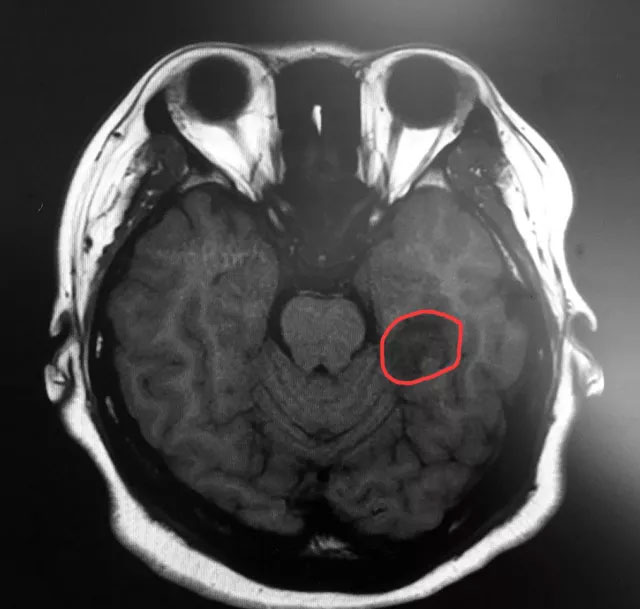

▲標記處為患者腫瘤部位

近日,上海藍十字腦科醫(yī)院神經(jīng)外科6B病區(qū)收治了一名癲癇患者。今年三月初,25歲的袁女士(化名)突然出現(xiàn)“陣發(fā)性無法對答、閉目、呆立不動、吞咽唾液、意識喪失”等癥狀,一個月偶爾發(fā)作一次,當時患者和家人也沒在意。但近三個月患者發(fā)作頻繁,嚴重時一天多達三四次,家人明顯感覺不對勁,之后就診于當?shù)蒯t(yī)院,并進行了頭部MRI檢查,影像學(xué)顯示:患者左側(cè)顳葉(海馬區(qū))囊實性占位。

據(jù)吳治群博士介紹,袁女士的癲癇比較特殊,她不單單是左側(cè)顳葉(海馬區(qū))囊實性占位引起的癲癇,同時還合并額葉癲癇,這種情況在臨床中也是不多見的。對于繼發(fā)性癲癇的治療,吳治群博士指出,首先要去除引起患者癲癇的因素,這樣對因治療效果才會更好;而袁女士左側(cè)顳葉(海馬區(qū))明顯占位,屬于繼發(fā)性癲癇,病因明確,通常首選手術(shù)治療癲癇。

隨后,醫(yī)院特邀功能神經(jīng)外科主任楊忠旭博士進行會診,綜合患者各項檢查結(jié)果,并結(jié)合其兩次影像檢查及24小時腦電監(jiān)測結(jié)果,一致認為患者為左側(cè)顳葉深部(海馬區(qū))占位繼發(fā)癲癇與左側(cè)額葉原發(fā)性癲癇。